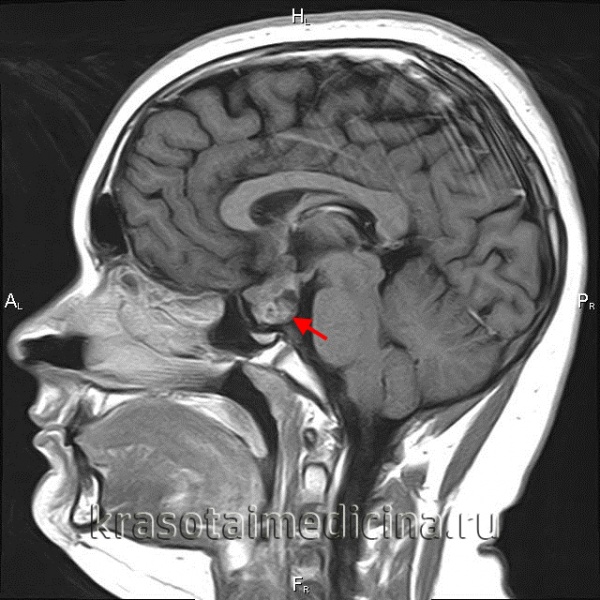

Нейровизуализацию опухоли гипофиза позволяет осуществить рентгенография черепа и зоны турецкого седла, МРТ и КТ головного мозга. Рентгенологически могут определяться увеличение размеров турецкого седла и эрозия его дна, а также увеличение нижней челюсти и пазух носа, утолщение костей черепа, и расширение межзубных промежутков. С помощью МРТ головного мозга возможно увидеть опухоли гипофиза диаметром менее 5 мм. Компьютерная томография подтверждает наличие аденомы и ее точные размеры.

С целью визуализации аденомы проводят рентгенографию турецкого седла, которая выявляет костные признаки: остеопороз с разрушением спинки турецкого седла, типичную двуконтурность его дна. Дополнительно используют пневмоцистернографию, которая определяет смещение хиазмальных цистерн от их нормального положения.

Более точные данные могут быть получены в ходе КТ черепа и МРТ головного мозга, КТ турецкого седла. Однако около 25-35% аденом гипофиза имеют настолько малый размер, что их визуализация не удается даже при современных возможностях томографии. Если есть основания считать, что аденома гипофиза растет в сторону кавернозного синуса, назначают проведение ангиографии головного мозга.

Высокоинформативным методом при подозрении на пролактиному является МРТ головного мозга с прицельным исследованием гипофиза контрастирующим веществом гадолиниумом. Магнитно-резонансное сканирование позволяет выявить очертания небольших аденом, их интраселлярное или экстраселлярное расположение, а также опухоли, расположенные в мягкотканных образованиях (кавернозном синусе, в области сонных артерий и т д.).

При макропролактиномах более применимо КТ головного мозга, т. к. хорошо визуализирует костные структуры (основание турецкого седла – анатомическую область расположения гипофиза).